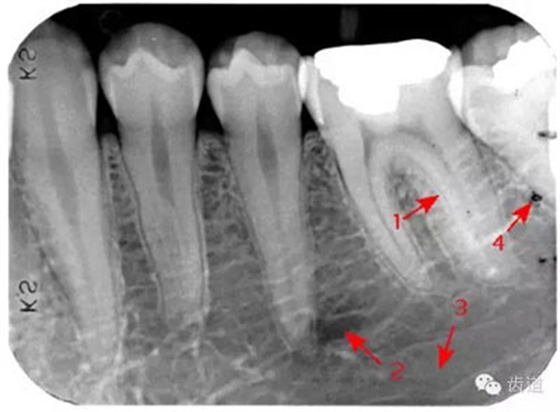

是機(jī)體中鈣化最高和最堅(jiān)硬的組織,X線片上的影像密度也最高,似帽狀被覆在牙冠部牙本質(zhì)的表面。后牙頜面、前牙切緣最厚,由頜面和切緣向側(cè)方至牙頸部逐漸變薄,終止于牙頸部。

牙頸部Burnout征象:有時(shí)因投照技術(shù)問(wèn)題而造成牙頸部近中或遠(yuǎn)中呈低密度影像,位于牙釉質(zhì)和牙槽嵴頂之間。

圍繞牙髓構(gòu)成牙的主體,牙本質(zhì)中礦物質(zhì)的含量比釉質(zhì)少,X線影像的密度較牙釉質(zhì)稍低。

被覆在牙根表面,為一層很薄的組織,密度與牙本質(zhì)相當(dāng) 。

髓腔可分為冠部的髓室和根部的根管。牙髓內(nèi)含牙髓軟組織,X線片上顯示為密度低的影像。年輕人的牙、牙根未完全形成時(shí),根尖孔粗大,牙髓腔大。隨著年齡的增長(zhǎng),牙本質(zhì)逐漸增多,髓腔愈狹窄,根尖逐漸變細(xì)。

即固有牙槽骨,是牙槽骨的內(nèi)壁,圍繞牙根,骨質(zhì)致密而薄,X線片上顯示為包繞牙根的連續(xù)不斷的密度高的線條狀影像。

是介于牙槽窩和牙骨質(zhì)之間的結(jié)締組織。牙周膜的厚度一般在0.15~0.38mm之間。X線上顯示為包繞牙根連續(xù)不斷的密度低的線條狀影像,其寬度均勻一致